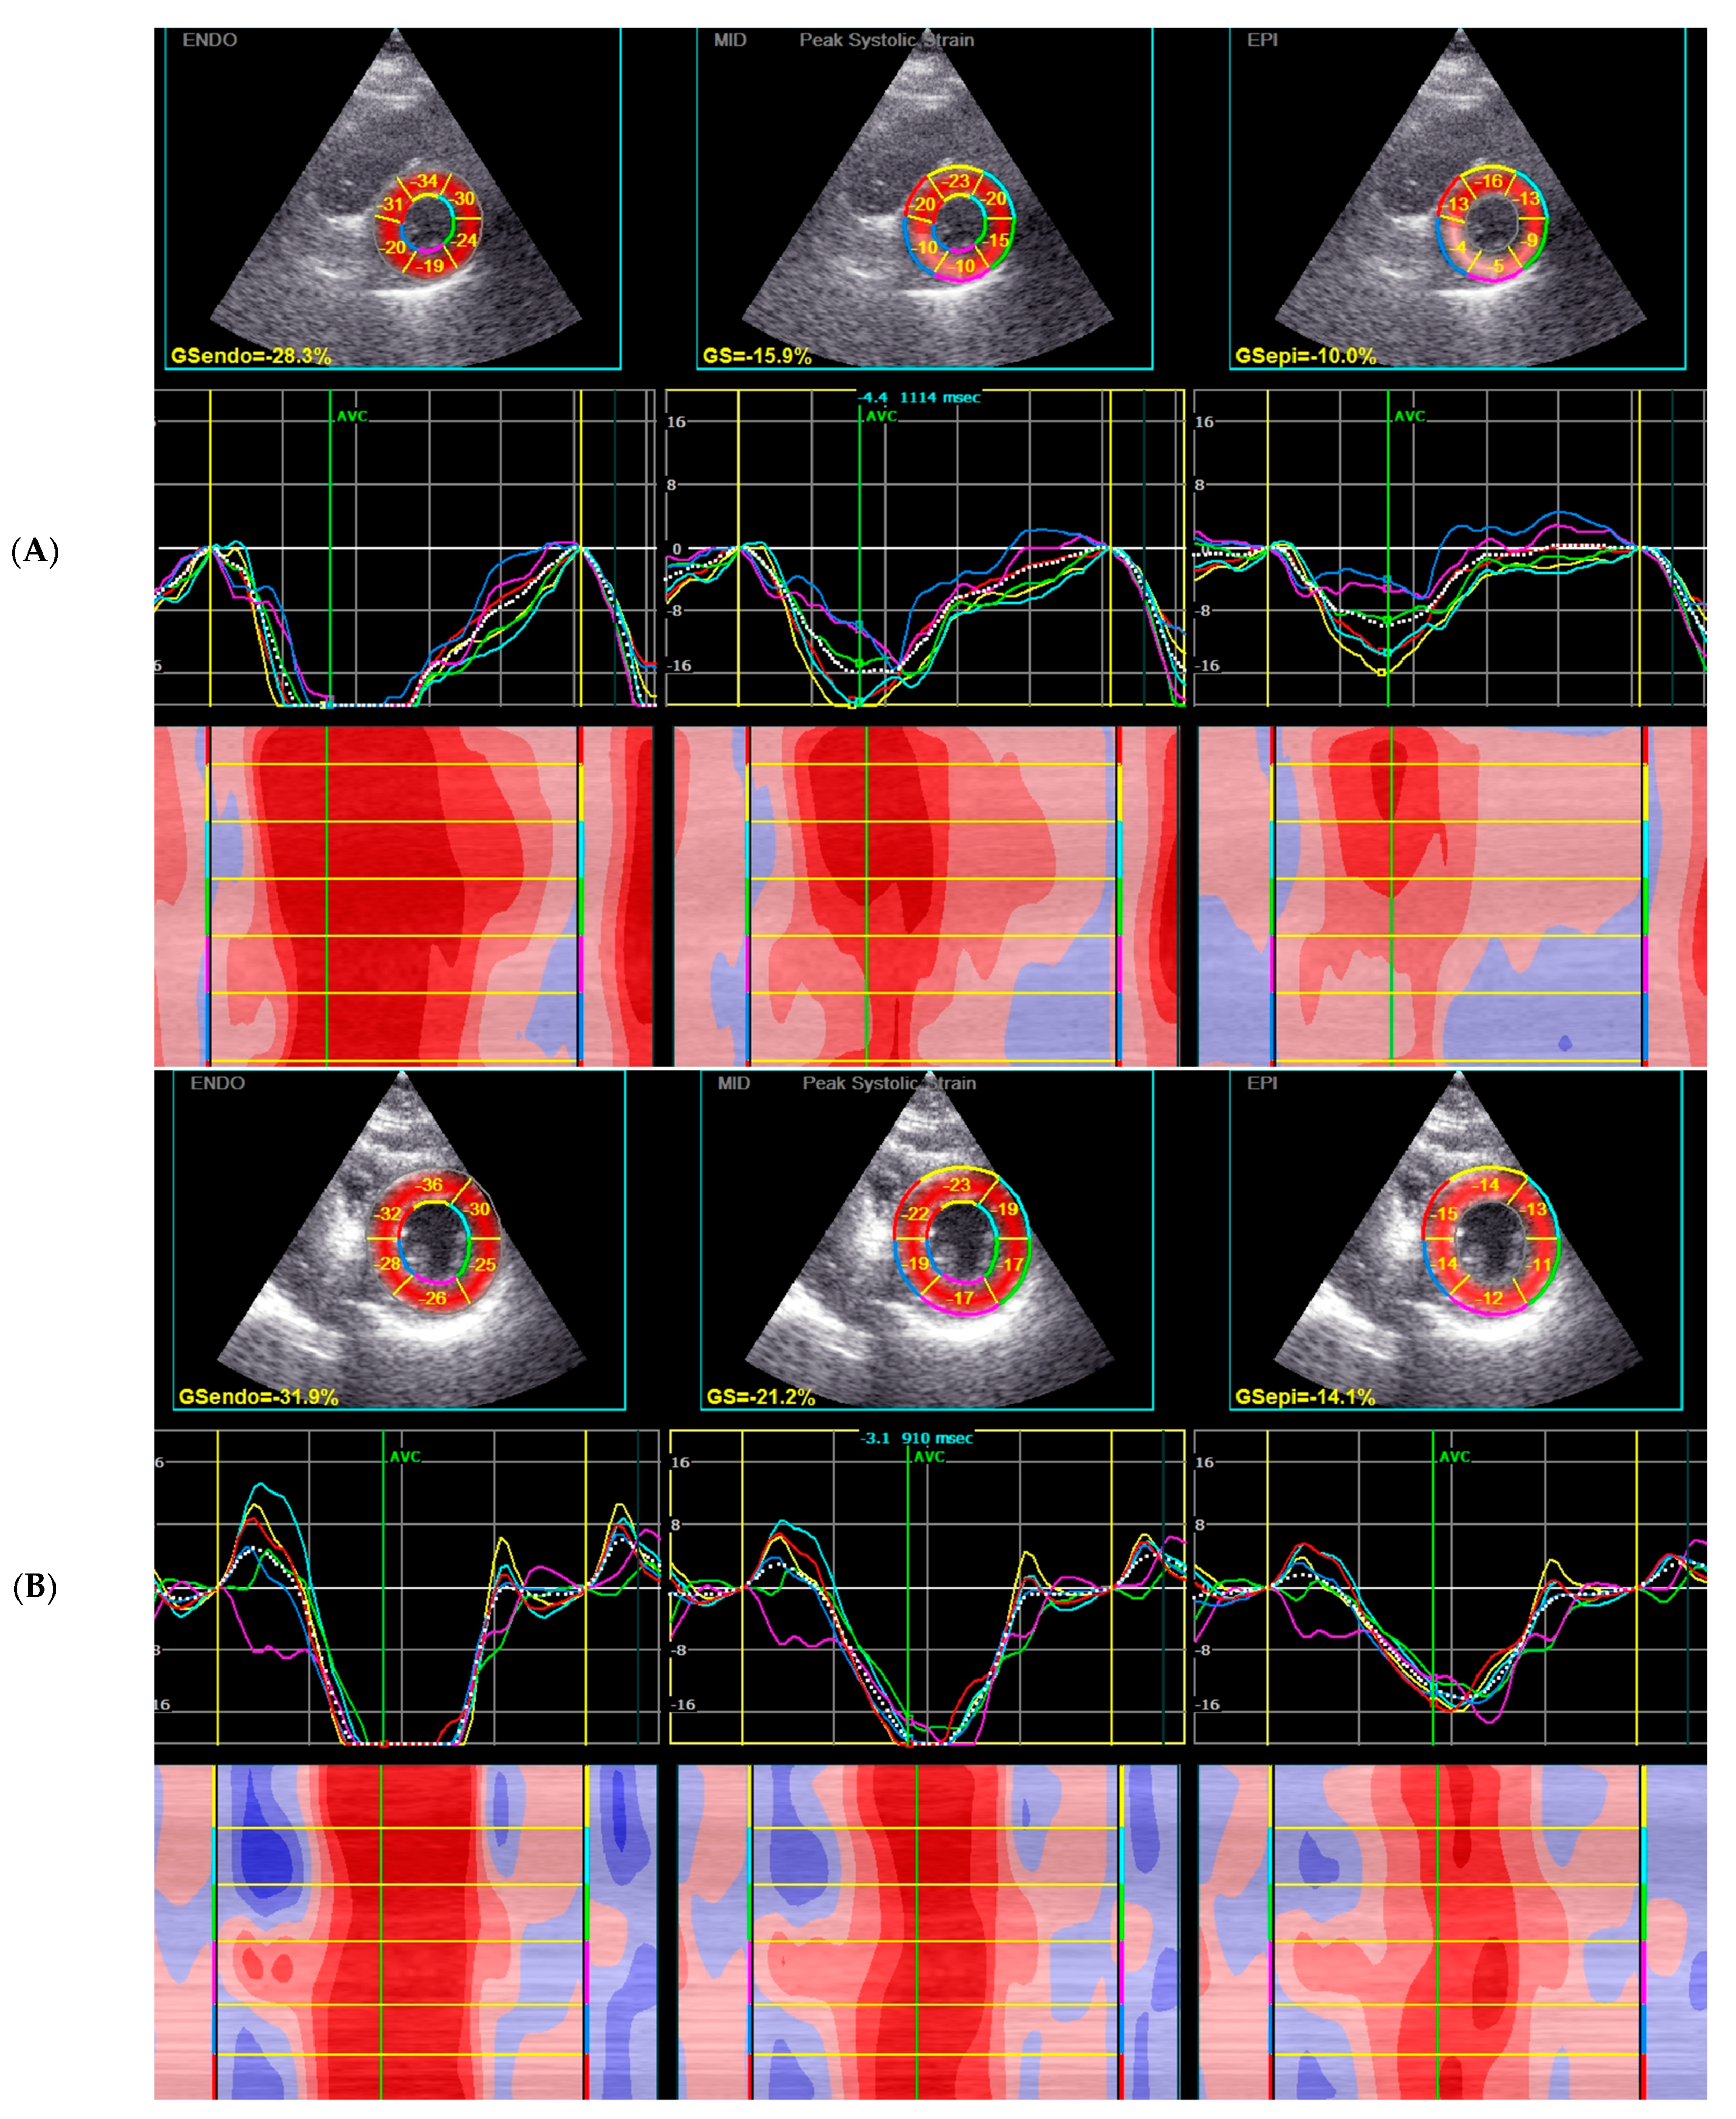

| GCS, % | −17.9 (−20.1–−15.3) | −16.8 (−18.4–−14.5) | −20.0 (−25.3–−17.3) | 0.001 |

| GCS MID systolic strain | −17 (−14.4–−19.4) | −15.7 (−17.2–−13.7) | −19.6 (−23.8–−16.6) | 0.000 |

| GCS EPI systolic strain | −10.6 (−13.5–−8.9) | −9.5 (−12.0–−7.5) | −12.7 (−15.9–−10.0) | 0.003 |

| GCS ENDO systolic strain | −26.2 (−29.8–−22.4) | −24.8 (−26.2–−20.8) | −28.8 (−35.8–−25.8) | 0.001 |